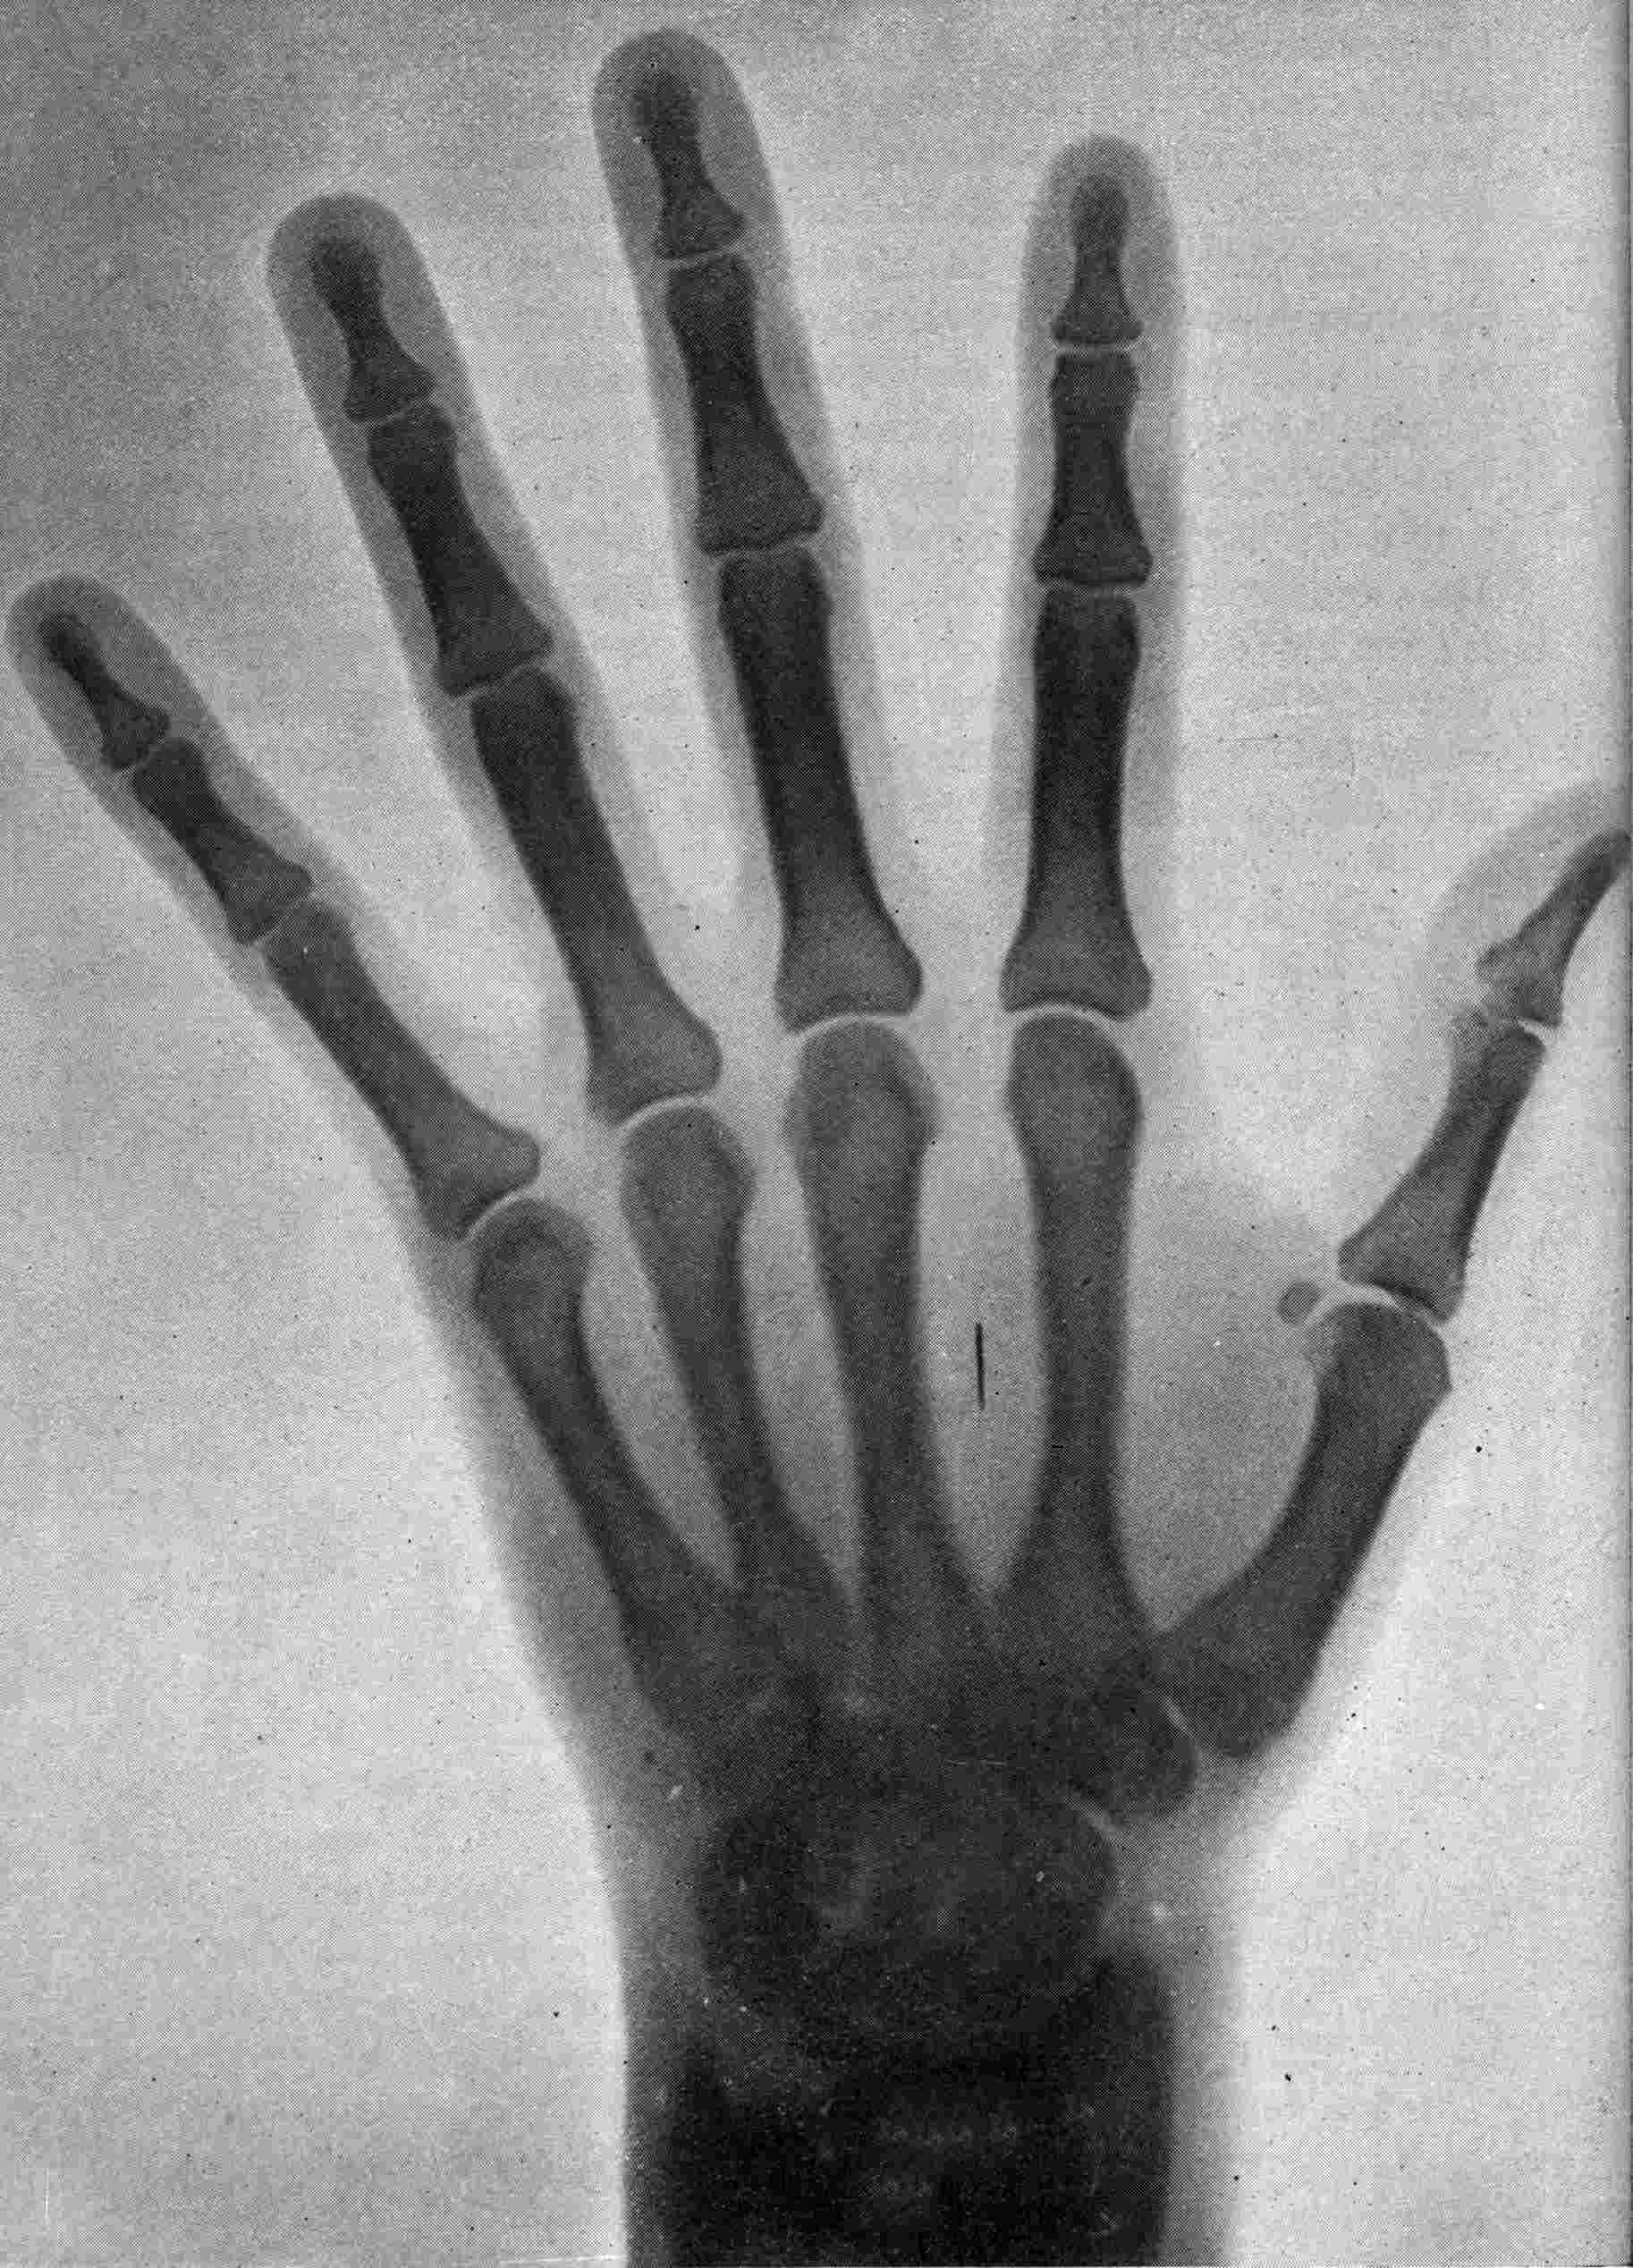

Fig. 1.—Head.

Fig. 2.—Broken Arm, Overlapping.

(Due to defective setting.)

Fig. 3.—Ribs.

Fig. 4.—Knee, Knickerbocker Buttons, Bullet in Femur.

FROM SCIAGRAPHS BY PROF. DAYTON C. MILLER. § 204.